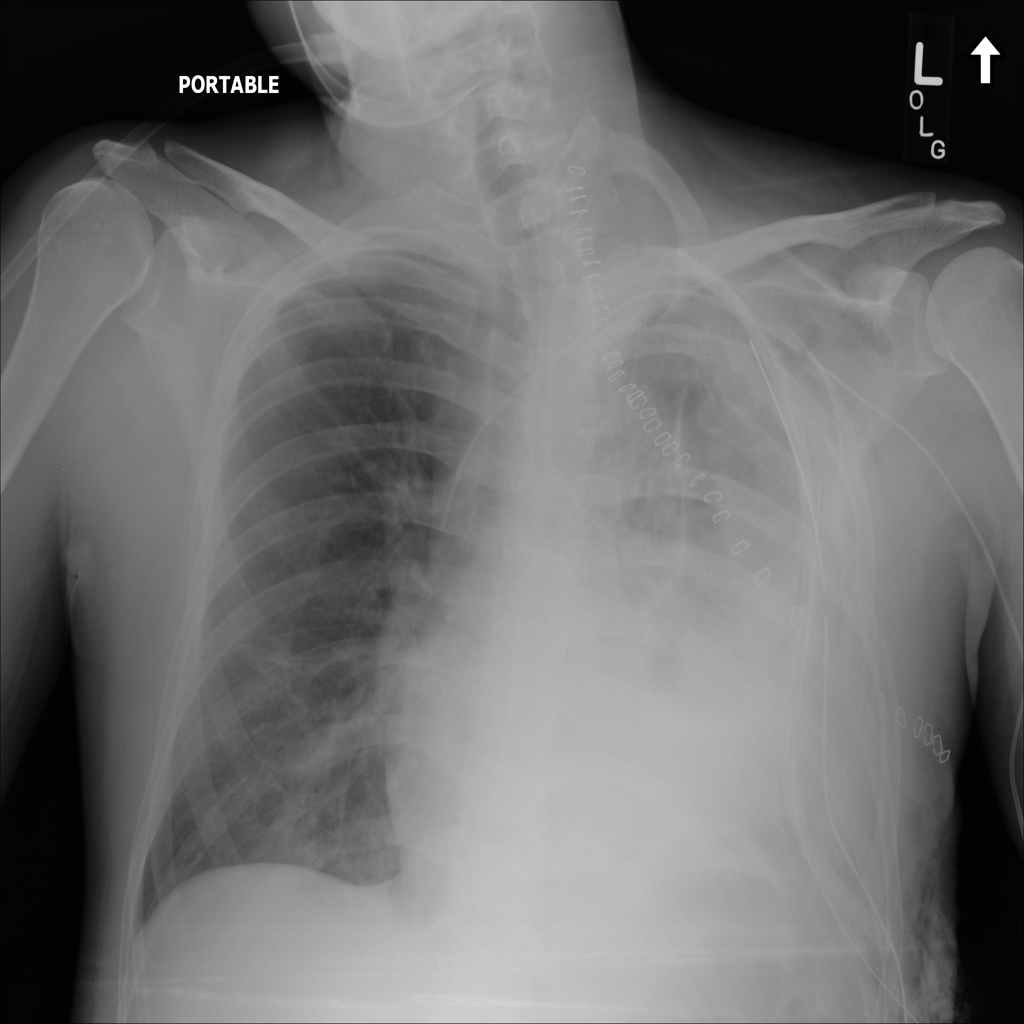

Showing up to 90 reference images for Emphysema.

PAT-0E82 · IMG-000Emphysema

PAT-0E82 · IMG-000

AP